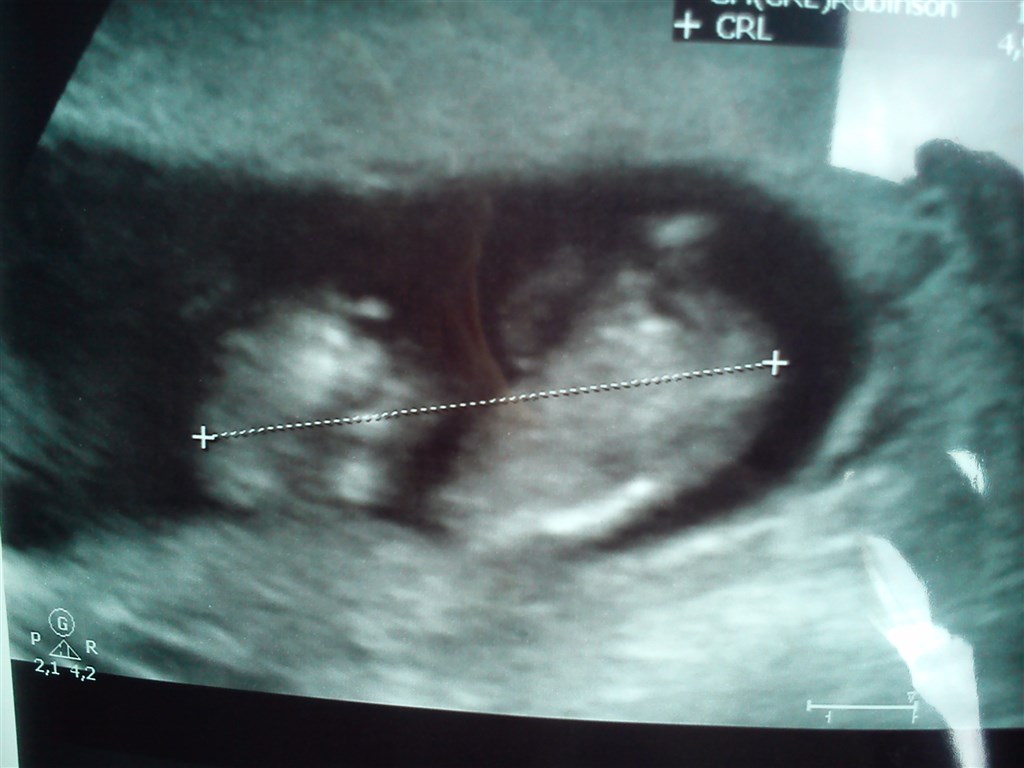

Vi skal til NF i morgen og kan slet ikke vente. Vi har været til en scanning for et par uger siden for at se om der nu også var noget og for at se hvor langt jeg ca var henne da min mens havde været lidt uregelmæssig.

Så får i også lige nogle billeder af mine teste, scanningsbilledet fra ts scanningen, mine stolte drenge og maven <3